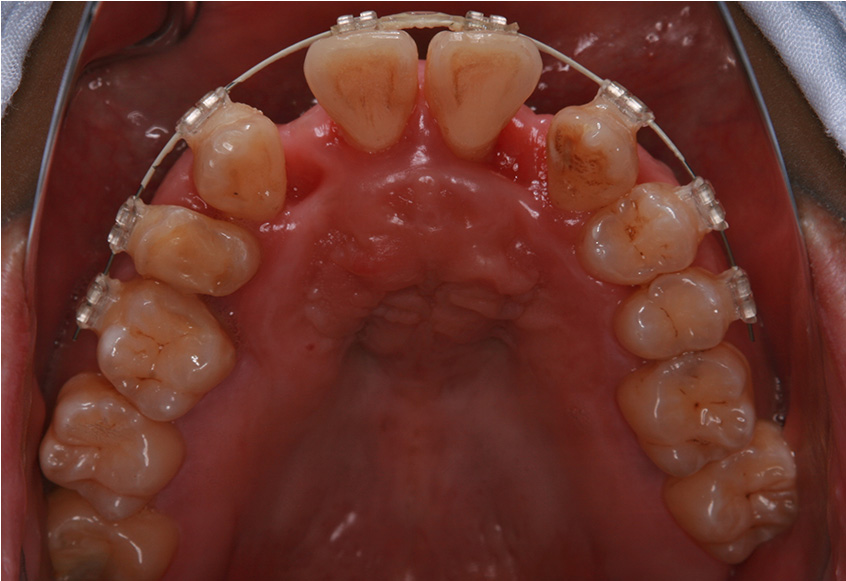

最初のお口の中 ワイヤー装着して治療を開始

-

治療開始後3ヵ月経過すると、前歯の隙間や全体の乱れが減ってきました。口笛が吹けるようになったとのことです。

最初のお口の中 治療開始3ヵ月後

| 矯正装置 | 矯正ブラケットとワイヤー |

| 治療内容 | 上顎側切歯を2本抜歯した後、上顎の歯にブラケットを装着し、ワイヤー、矯正用ゴムで歯の移動を行いました。その後、被せ物の治療を行って治療を終了しています。 |